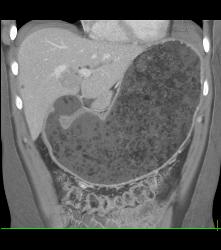

Antral Carcinoma- See Sequence